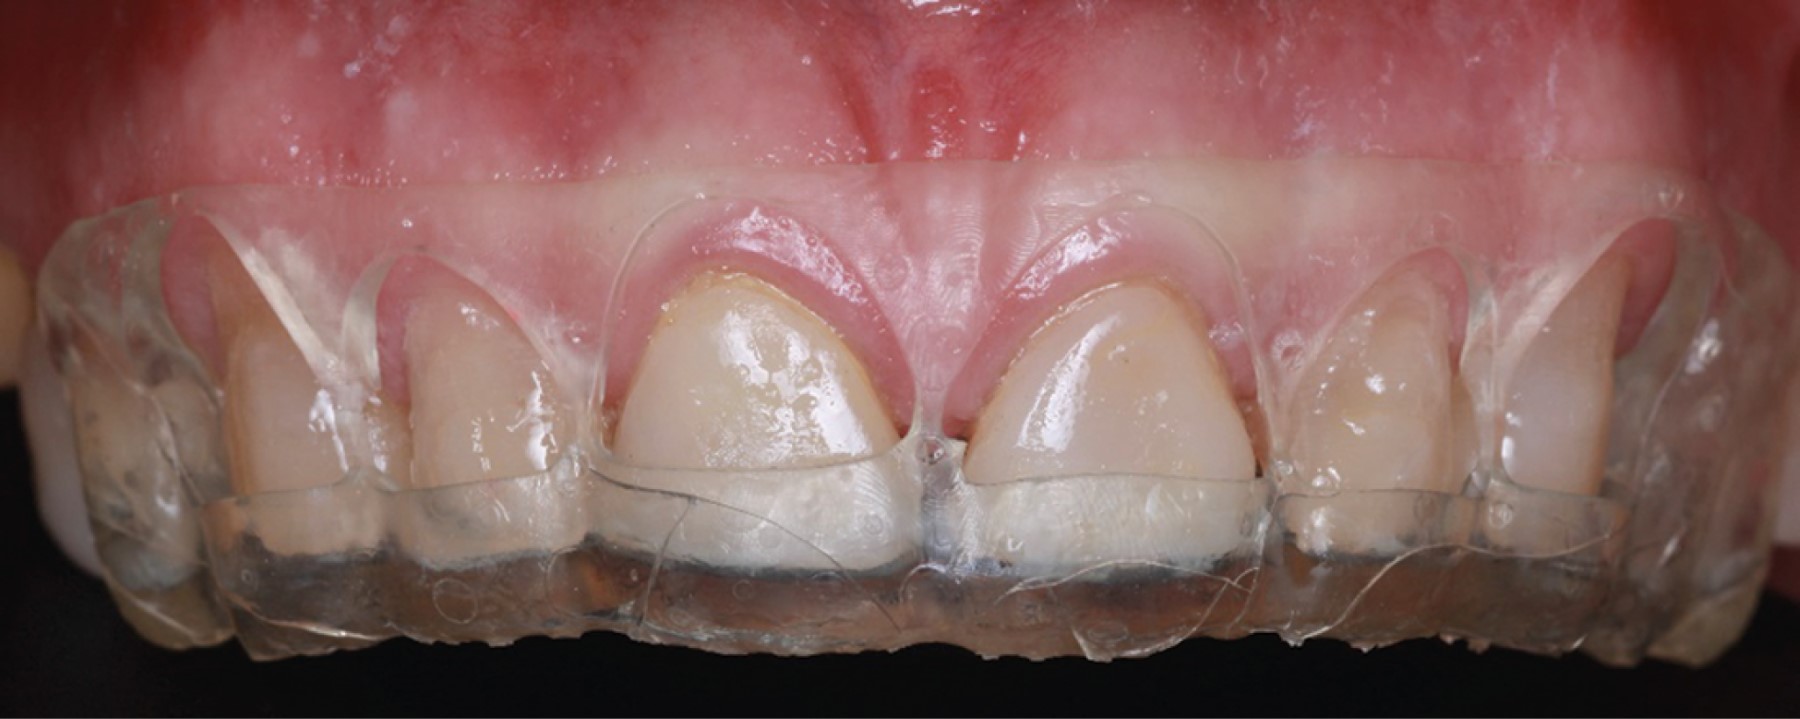

Introduction: crown lengthening for aesthetic purposes aims to reveal an adequate crown length and reduce gingival exposure. The procedure includes gingivectomy and alveolectomy to restore the prosthetically required supracrestal gingival tissue according to physiological dimensions. Through an intraoral scan of the maxilla, mandible, and maximum intercuspidal position, and using specialized software, the shape of the teeth and the gingival contour are digitally designed. This design generates an image of the desired aesthetic restoration for the prosthodontist and periodontist. The physical fabrication of the design is computer-assisted (CAD-CAM), creating a vacuum-formed acrylic resin surgical guide to determine the clinical crown length required in surgery. Objective: the presented interdisciplinary case describes an innovative technique using digital workflow through software that, from an oral scan, digitally designs a Mock-Up used as a guide for periodontal surgery. Case presentation: a 52-year-old ASA I patient attended the Periodontics Master's clinic at Universidad Autónoma de Coahuila (UAdeC) for periodontal surgery with aesthetic purposes. The surgery was performed by placing the Mock-Up in the anterosuperior region as a guide for gingivectomy. Then, a flap was raised before the alveolectomy, considering the length of the supracrestal gingival tissue. Finally, the soft tissues were sutured with a horizontal mattress suture technique. Results: seven days later, the sutures were removed, showing correct and uniform tissue healing. Conclusions: this digital approach offers a significant reduction in surgical time, in addition to satisfactory esthetics and precise gingival architecture.

Figure 2